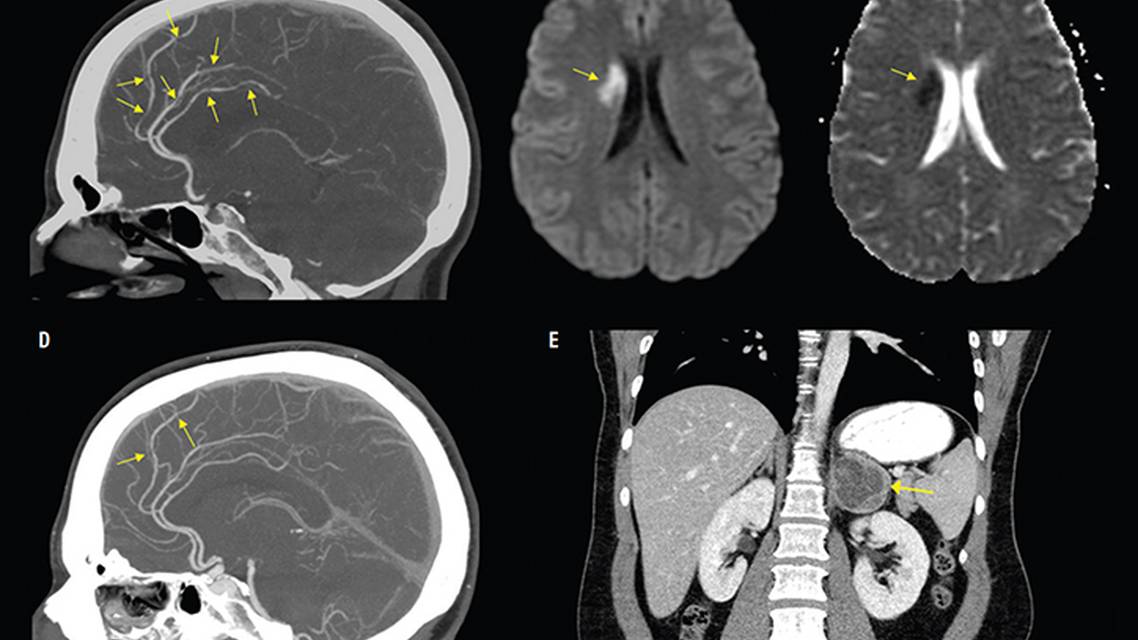

Over the subsequent days, NS experienced 2 additional attacks of thunderclap headache with concurrent chest pain, prompting a return to the emergency department. At the second emergency department visit, troponin levels were within normal limits. CT head did not show hemorrhage. CT angiogram revealed multifocal narrowing of the distal intracranial arteries for which the differential diagnosis included reversible cerebral vasoconstriction syndrome (RCVS) and vasculitis. Conventional cerebral angiography confirmed the presence of multifocal areas of mild smooth narrowing of the branch vessels of the anterior and middle cerebral arteries bilaterally (Figure 1A). MRI of the head revealed an acute infarct involving the right caudate body extending into the white matter (Figures 1B, 1C), as well as additional punctate foci of diffusion restriction throughout the right hemisphere, reflecting acute infarcts. Lumbar puncture revealed normal glucose, increased protein (74 mg/dL), and normal cell count, with an opening pressure of 23 cm (Table 1). NS was discharged on nimodipine with a diagnosis of RCVS.

One week after discharge, after a massage, NS developed severe headache, chest pain, and black spots in the field of vision lasting about 30 minutes. NS was seen urgently in neuro-ophthalmology and found to have left homonymous hemianopsia. NS was readmitted to the hospital. Repeat conventional angiography showed significant improvement in vessel caliber, although there was persistent focal narrowing of the right pericallosal artery (Figure 1D), which improved with verapamil infusion, and NS was discharged.

Over the subsequent 2 months, NS continued to have headache on a near daily basis, lasting the majority of the day, interspersed with bouts of thunderclap headaches and chest pain, leading to readmission. During the third admission, NS described an area on the back where applying pressure seemed to trigger thunderclap headache. Imaging of this area, including thoracic MRI followed by abdominal CT, revealed a left adrenal gland mass (Figure 1E). Plasma and urine metanephrines were significantly elevated (plasma normetanephrine, 9.0 nmol/L [normal <0.90]; metanephrine, 3.0 nmol/L [normal <0.50]) (Table 1). The left adrenal gland mass was resected, resulting in a final pathologic diagnosis of pheochromocytoma.